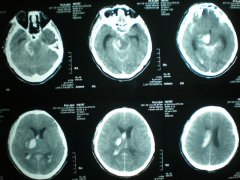

腦卒中是由于腦部血管突然破裂或因血管阻塞導致血液不能流入...